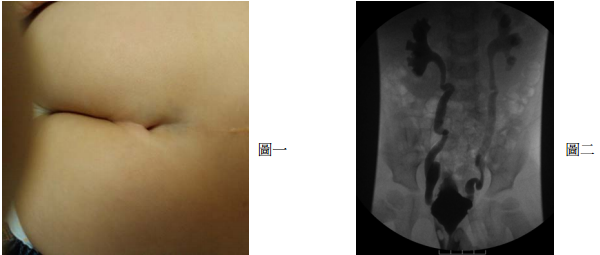

31 一位 2 歲大的女嬰出生時即發現背後有一個如圖一的皮膚病灶。最近因反覆泌尿道感染住院。膀 胱尿道攝影檢查(voiding cystourethrogram)顯示如圖二。下列何種處置方式最恰當?

(A)應立即作輸尿管重植術,以避免腎傷害 (B)給予低劑量抗生素,預防感染,等待自然恢復 (C)訓練照顧者作間歇性導尿 (D)施予雙側輸尿管口之玻尿酸注射